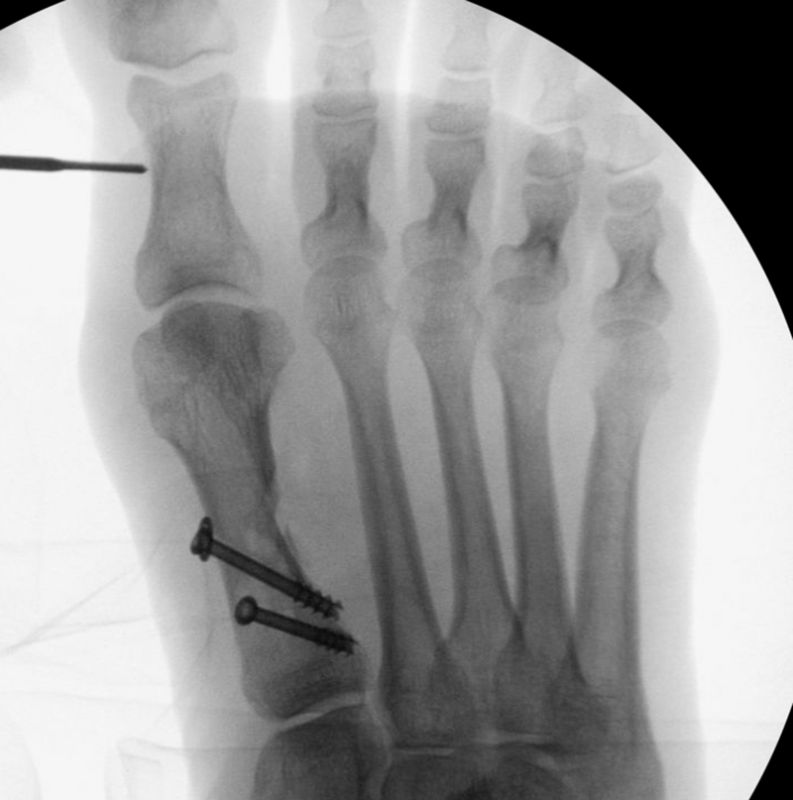

• Kanülierte Schrauben bis 50 mm Länge, 4 mm Durchmesser, Beilagscheiben.

• Gute Stabilität durch Stabilisierung mit einer oder zwei perkutanen Schrauben möglich.

• Röntgenkontrollen (Vorfuß d.p. und seitlich) postoperativ ohne Belastung. Weitere Kontrollen erfolgen 6 Wochen, sowie 3, 6 und 12 Monate jeweils unter Belastung.

• Bruch der medialen Kortikalisbrücke mit Verkürzung und Elevation des 1. Strahles. In diesem Fall muß die Länge des 1.Strahles durch eine quer zur Schaftachse plazierten Schraube gesichert werden. Als Alternative bietet sich eine lange Schraube durch den Schaft als intramedullärer Kraftträger an

• Bei hohem Hallux valgus Winkel oder pathologischem Gelenkflächenwinkel besteht die Indikation zu einer zusätzlichen Isham Osteotomie 2, die im Wesentlichen der offenen Reverden Green Osteotomie entsprecht.